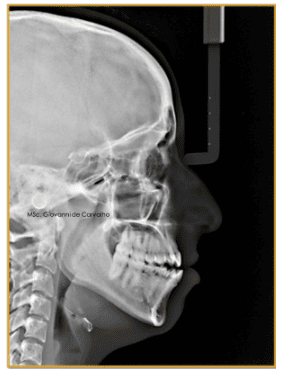

Durante a primeira avaliação, percebemos que Thaís tinha um perfil convexo, ou seja, o lábio inferior se projetava para frente, dando a sensação de que a boca estava sempre "forçando" o fechamento. Ela tinha todos os dentes permanentes, exceto os sisos, mas dois dentes importantes nunca se formaram: os incisivos laterais superiores. Além disso, mais tarde descobrimos também a ausência dos segundos pré-molares inferiores.

Sua mordida mostrava características típicas de Classe II, com dentes superiores inclinados para trás e uma mordida aberta de 2 mm, ou seja, os dentes da frente não se encontravam quando ela fechava a boca. Era um caso complexo, que exigia uma combinação de estratégias para devolver equilíbrio, estética e função.

Esse tipo de alteração é conhecido em Ortodontia como Classe III de Angle, um nome técnico para um problema em que os dentes de baixo ficam mais para frente do que os de cima, causando a chamada "mordida cruzada" ou "mordida invertida". Esse tipo de desarmonia pode afetar o encaixe da mordida, o sorriso e até a estética facial.